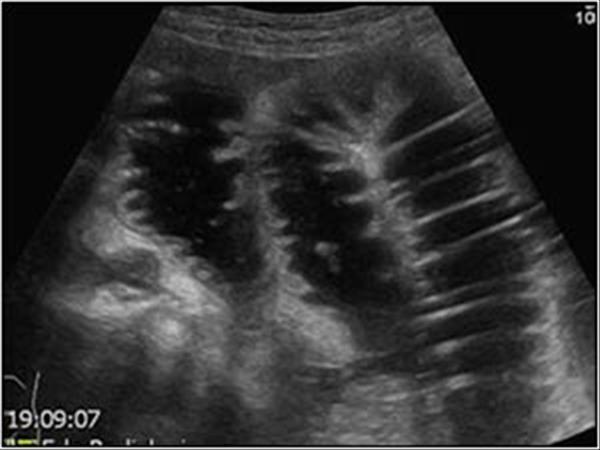

Small bowel Obstruction

Colon obstruction

vomiting

abdominal pain

rectal bleeding

Intussception

vomiting

abdominal pain

rectal bleeding

Intussception